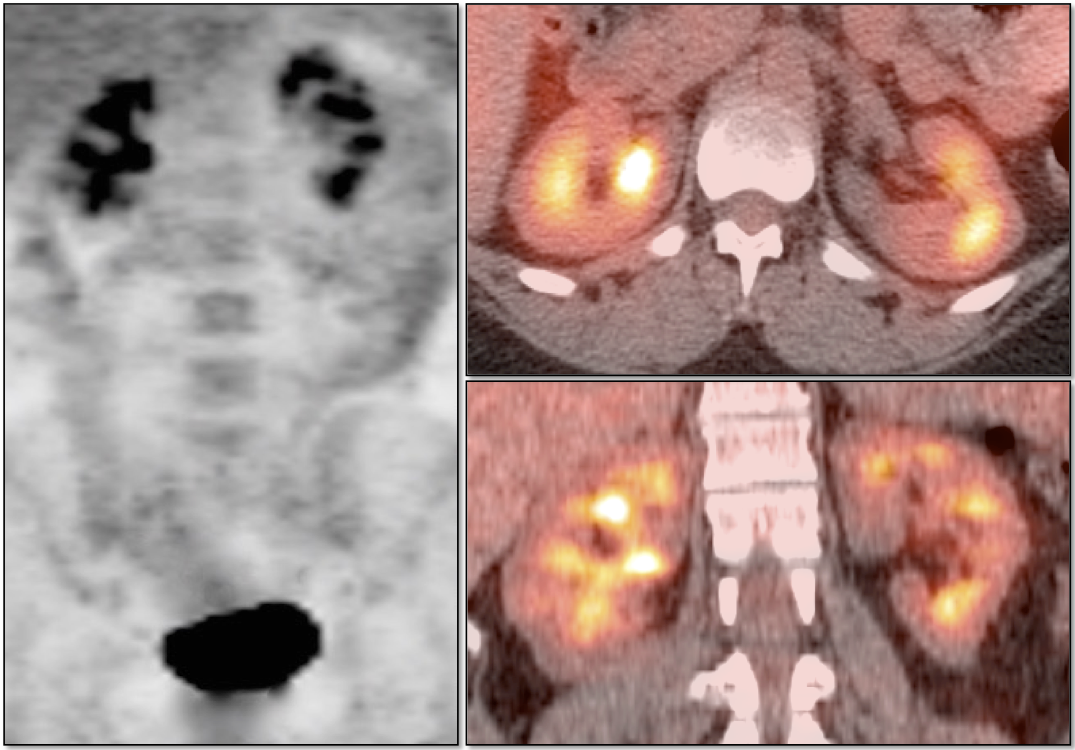

Metastatic Disease: Metastatic RCCA lesions are usually more FDG avid than the primary lesion (nearly all demonstrate metabolic activity greater than liver uptake).

• Direct invasion of adjacent structures.

• Tumor thrombus into renal vein must be excluded.

• Hematogenous spread, often to lungs, bone, liver, and brain.

• Lymphatic spread to regional and distant lymph nodes.